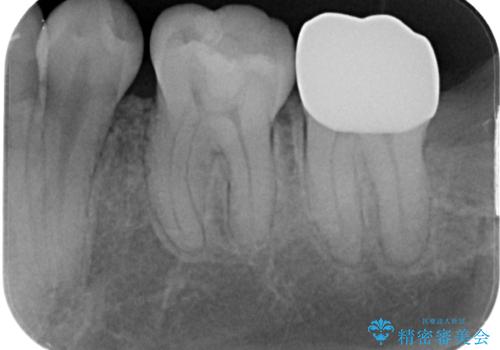

歯茎の治癒を3か月程度待ち、最終的なフルジルコニアクラウンの形に整え精密な型どりをシリコーン印象材にて行っております。

精密印象時、舌がよく動いたり唾液の量も多かったため個歯トレーを使用しています。

機能面、見た目ともに大変喜んでいただきました。

歯茎の治癒を待つ間に痛み等ないことを確認できたので最終的な型どりを行いました。